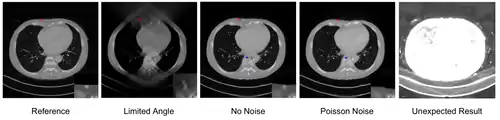

I metodi di apprendimento profondo sono ampiamente utilizzati per la ricostruzione di immagini e sono stati applicati in diversi ambiti, tra cui la riduzione del rumore nelle tomografie a bassa dose di radiazioni, la ricostruzione con numero sparso di viste, la tomografia ad angolo limitato e la riduzione degli artefatti dovuti alla presenza di metalli. Una panoramica eccellente può essere trovata nell'edizione speciale della rivista IEEE Transactions on Medical Imaging[29]. Ad esempio, una delle maggiori tipologie di algoritmi di ricostruzione tramite deep learning applica reti neurali di post-processing per migliorare una ricostruzione già esistente, ottenuta in precedenza tramite metodi di ricostruzione convenzionali. Un esempio di applicazione è la riduzione degli artefatti utilizzando la rete U-Net nella tomografia ad angolo limitato[30].

In un'immagine ricostruita mediante un metodo completamente basato sui dati usando come input il sinogramma, possono tuttavia verificarsi degli errori. Pertanto, l'integrazione di operatori noti nella progettazione dell'architettura delle reti neurali potrebbe risultare vantaggiosa, come descritto nel concetto di apprendimento di precisione[31]. Ad esempio, la ricostruzione diretta di immagini dai dati di proiezione può essere appresa dalla struttura dell'algoritmo di retroproiezione filtrata[32]. Un altro esempio è la costruzione di reti neurali mediante l'iterazione di algoritmi di ricostruzione[33]. Oltre all'apprendimento di precisione, un approccio alternativo per migliorare la qualità delle ricostruzioni ottenute tramite deep learning è utilizzare metodi di ricostruzione convenzionali applicati a una precedente ricostruzione basata su deep learning[34].